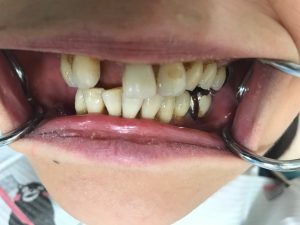

ウェルデンツ装着前の写真です。

この写真ではわかりやすいように、器具で口唇を引っ張っているので余計に目立ちますが・・・(;゜ロ゜)